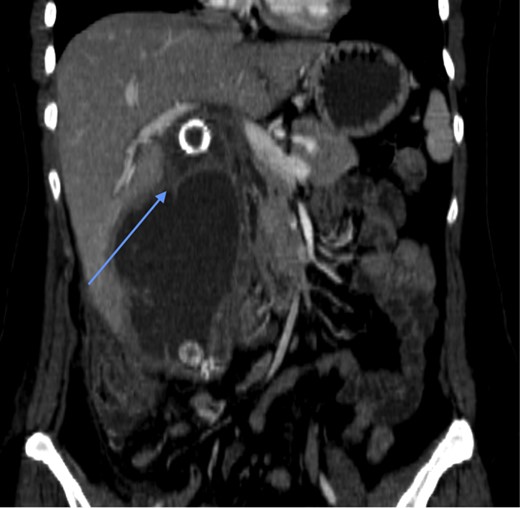

Laboratory investigations (biochemical profile and urinalysis) were all within normal limits. Abdominal CT showed pneumobilia and a 2 cm intraluminal density in the distal ileum with resultant small bowel obstruction (Figs 1 and 2). She underwent emergency laparotomy and enterolithotomy followed by a smooth postoperative course (Figs 3 and 4). The CT scan taken elsewhere and just prior to the emergency cholecystecomy 12 months earlier was reviewed; this demonstrated a markedly distended gallbladder with irregular wall thickening and severe pericholecystic fat stranding consistent with a gallbladder empyema measuring 16 cm × 9.0 cm. There were also multiple gallstones with the largest two measuring 2 cm at the neck of the gallbladder and the other, 2.0 cm in diameter at the fundus of the gallbladder, respectively. There was a narrower, septum-like area between the neck and grossly distended empyema (Fig. 5)

CT scan showing a rim-calcified gallstone, causing ileal obstruction.